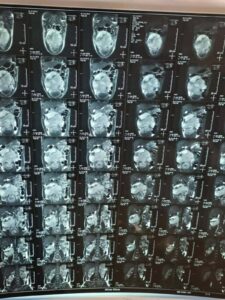

أجرى فريق طبي متخصص في مستشفى بغداد التعليمي التابع لدائرة صحة مدينة الطب عملية استئصال ورم بالأمعاء والأوعية الرئيسية في البطن لمريض يبلغ من العمر 25 عاماً، كان يعاني من انتفاخ كبير في البطن.

وذكرت إدارة المستشفى أنه بعد إجراء كافة الفحوصات الطبية والشعاعية اللازمة تبين وجود ورم متقدم في الأنسجة الرخوة للبطن، وتم إجراء العملية للمريض، حيث تم خلالها استئصال الورم الملتصق بالأمعاء والأوعية الرئيسية في البطن بصورة كاملة مع حواف سليمة والقولون الأيمن.